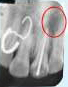

X-ray showing

picture line